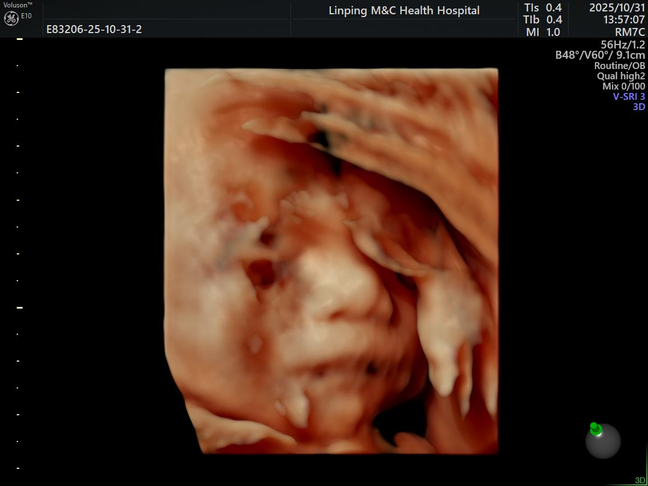

10.31 宝宝的四维照片

宝宝的四维照片